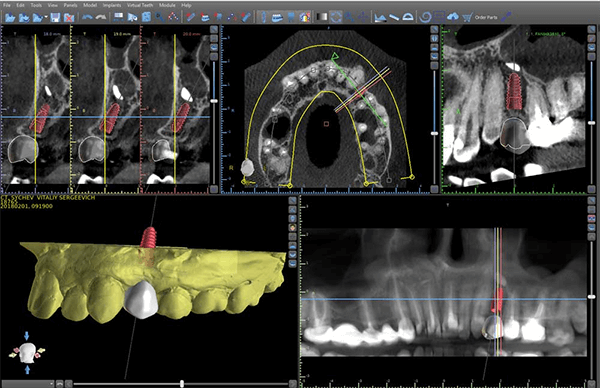

- Аппаратная диагностика. С помощью КТ определяет объем кости, глубину гайморовых пазух, расположение тройничного нерва. Затем проводит кондилографию для планирования этапа протезирования.

- План лечения. Данные после диагностики вносят в компьютерную программу. В ней врач конструирует объемную модель челюсти, рассчитывает точное расположение имплантов и фиксацию протеза. По 3D шаблону готовит хирургический шаблон, по которому будет ставить имплантаты.